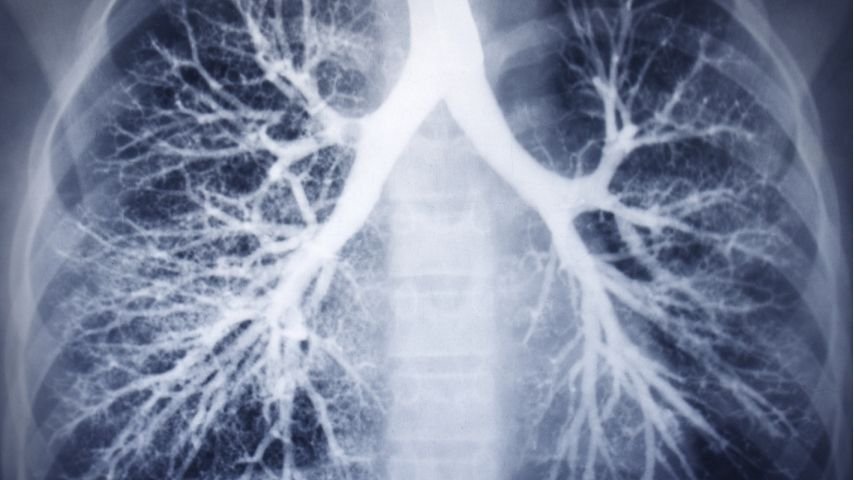

The lungs are complex organs responsible for breathing and supplying oxygen to the body. They are made up of delicate airways and tiny air sacs that allow oxygen to pass into the bloodstream.

The lungs contain a complex network of branching airways that extend from the windpipe into smaller and smaller passages. These airways become narrower as they travel deeper into the lungs.

This technology combines bronchoscopy with advanced computer guidance systems. Doctors use CT scan images to create a detailed three-dimensional map of the patient’s lungs.

The map shows the branching airway pathways and the exact location of the lung nodule. Doctors use this map to plan the best pathway to reach the target area.